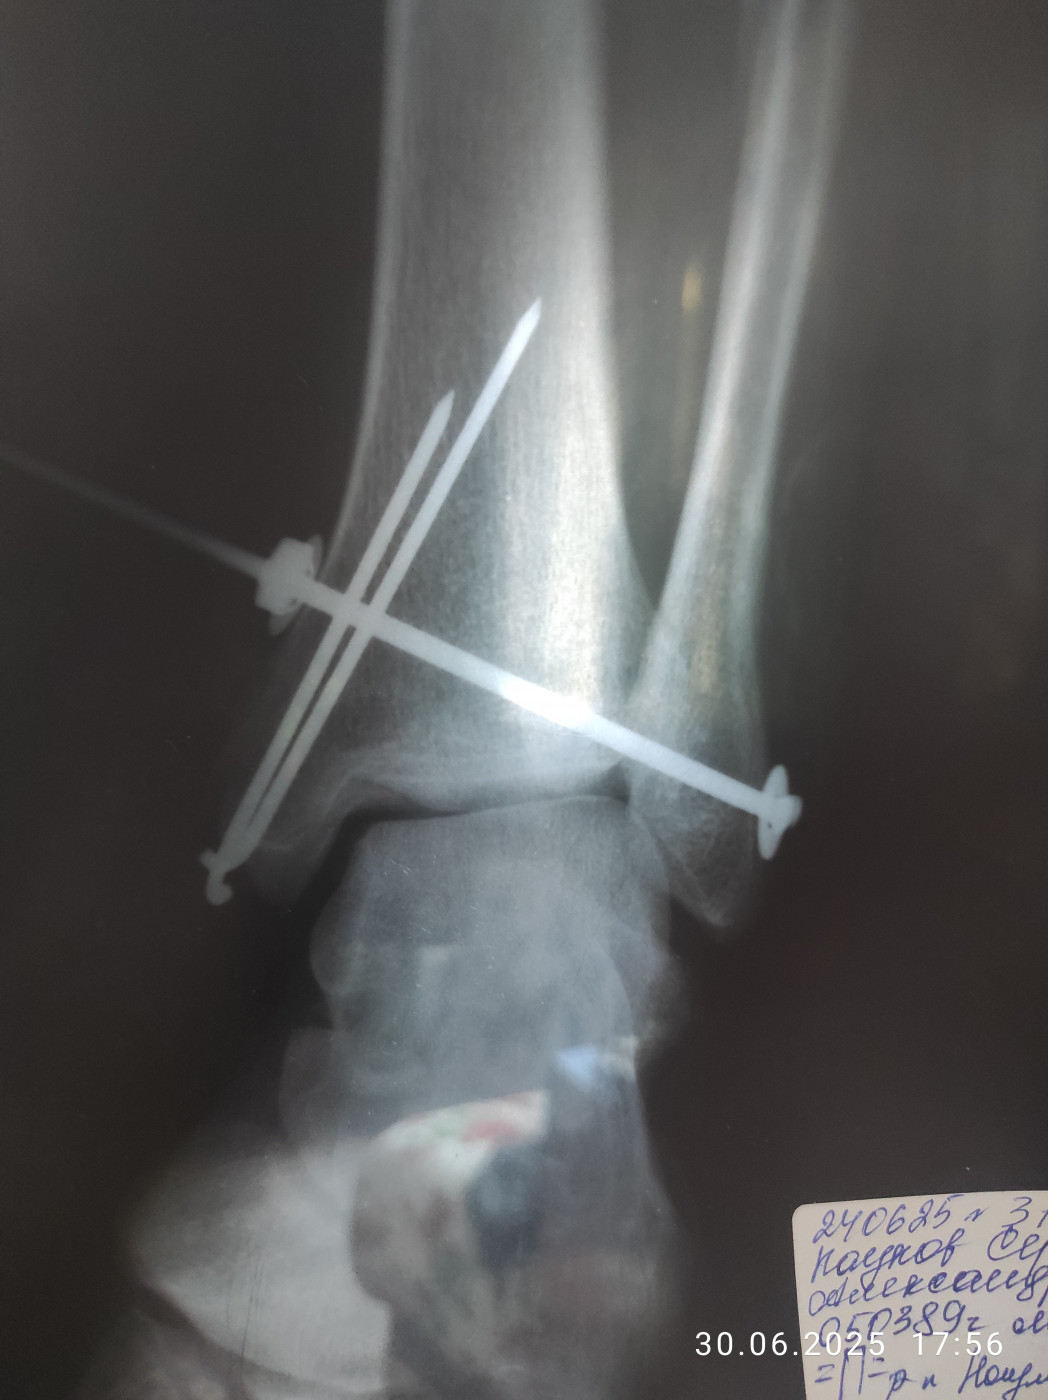

Перелом ноги   1 ответ

Здравствуйте. Диагноз: Закрытый перелом медиальной лодыжки со смещением отломков, перелом н/3

малоберцовой кости с незначительным смещением отломков и разрывом дистального

межберцового синдесмоза. Закрытый перелом заднего края большеберцовой кости без смещения в левом голеностопном суставе. Проведена операция. Какие последствия перелома и сроки восстановления? Особенно смещение малоберцовой кости которое осталось без изменений